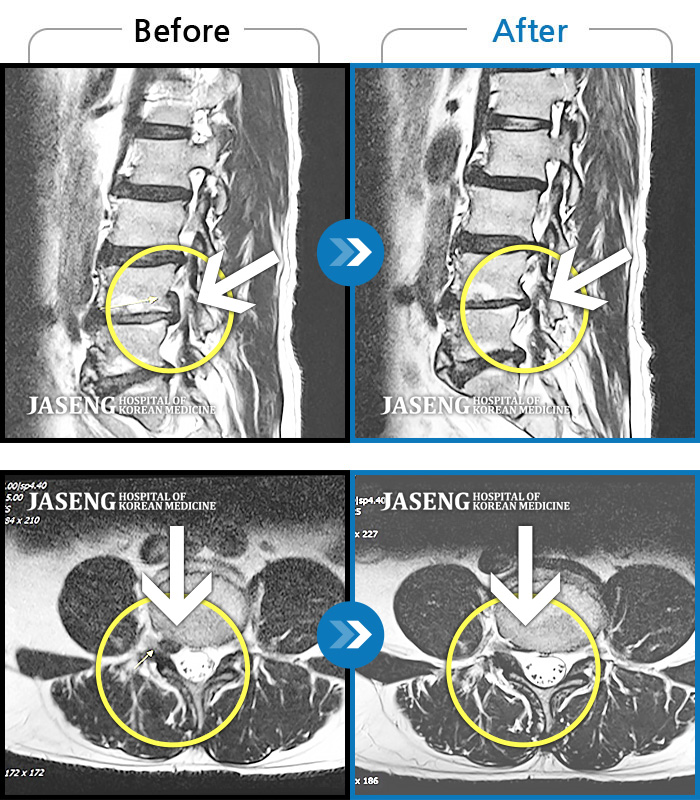

MRI 치료사례

허리 골반 통증, 우측 다리에서 종아리까지 저리고 당김, 야간통